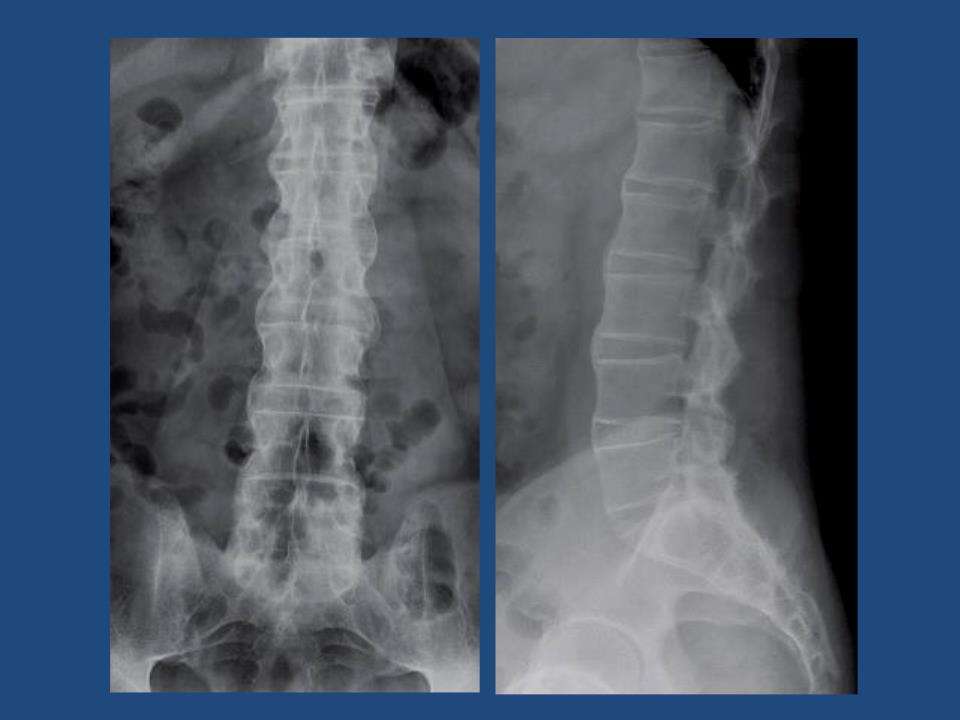

强直性脊柱炎这个疾病相信大家是不会感觉到陌生的,这个疾病在较近年的几年当中的发病率是越来越高了,引起强直性脊柱炎原因是有很多的,其中生活不规律也是其中的一个,强直性脊柱炎的发生是会给患者的身体健康带来很大的危害的,是患者要高度的重视的。